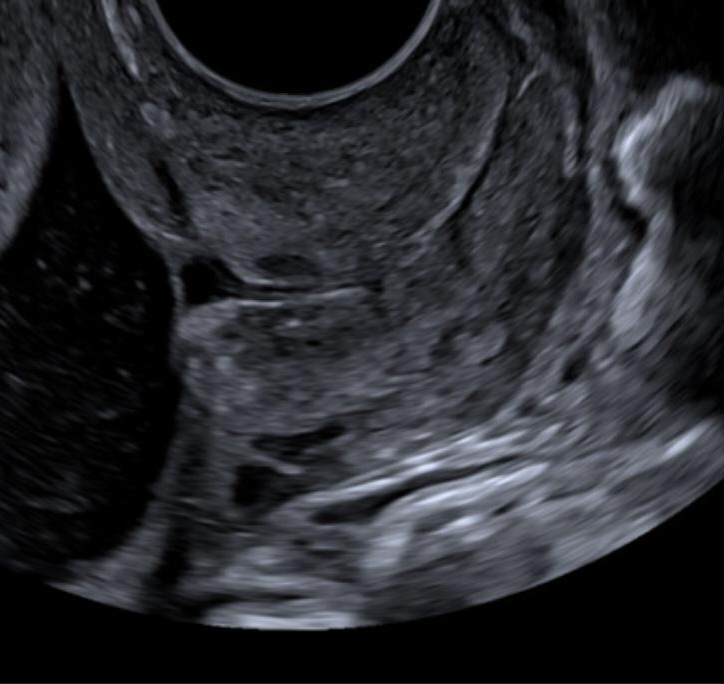

6. Uterine didelphis

Congenital uterine anomalies are a risk factor for preterm birth; however women are not always aware of their specific uterine anomaly. It is therefore always good practice to consider a uterine anomaly, such as uterine didelphis, when the cervix has an unusual appearance. If you suspect two cervical canals on longitudinal section, turn into transverse section to confirm the presence of two cervical canals (Fig 4).

Figure 4a. Longitudinal section showing two cervical canals

Figure 4b.  Transverse section showing to two cervical canals in cross section.